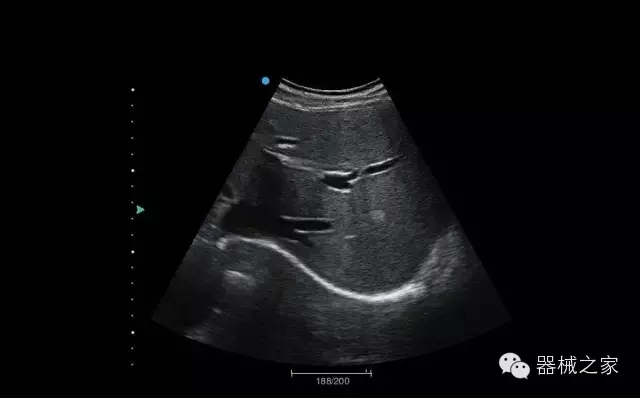

臨床圖片賞析

肝血管瘤